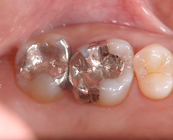

セラミックインレー

昔詰めた銀歯のお色が気になる方や金属アレルギーが心配な方へ

透明で美しく変色しにくい素材をおすすめします。見た目が天然歯に近い素材なので、区別がつきにくく年数がたっても変色しにくいことが特徴です。

Before

After